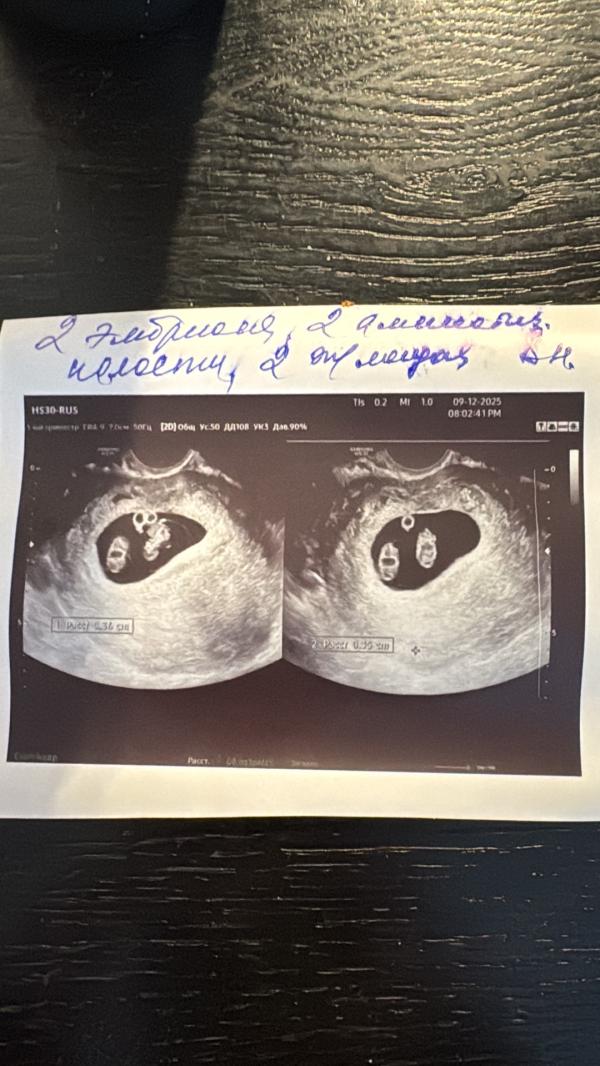

И…девочки, это ЧУДО! Я и подумать не могла, что увижу ДВОИХ ❤️❤️

P.S - монохориальная диамниотическая двойня.

Какая миома в плодном яйце? Как она туда попасть должна по вашему? 🤦♀️🤦♀️🤦♀️ желточные мешочки это

У неё монохориальная диамниотическая двойня. Плацента одна на двоих!

Это невозможно, если беременность моно-моно, как у автора

Дети будут сто процентов одного пола

Судя по фото, моно-моно